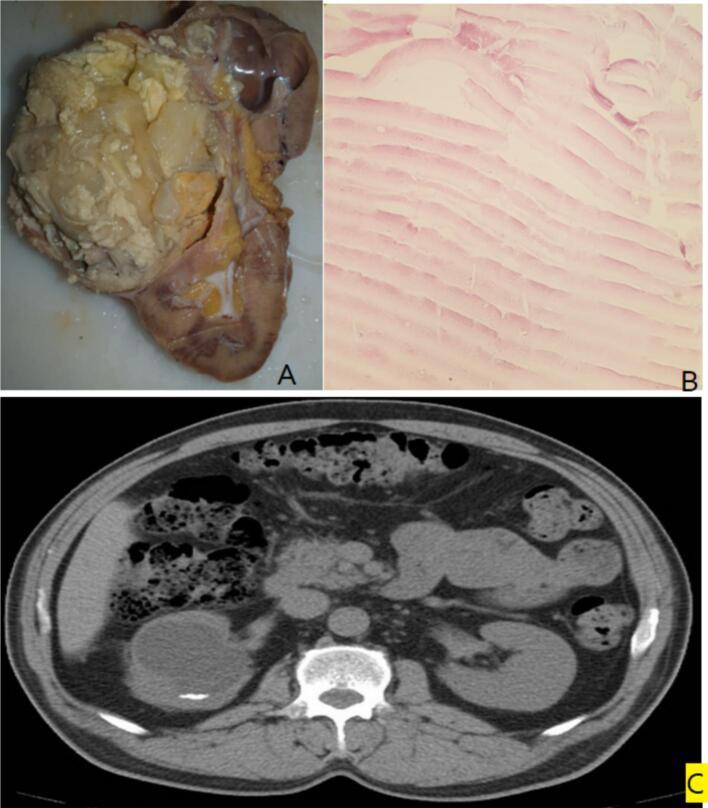

CASE PRESENTATION

We present the case of a 59-year-old woman with right flank pain and gross hematuria. Imaging, including ultrasound and a contrast-enhanced CT scan, revealed a large cystic lesion with calcifications in the right kidney, leading to a preliminary diagnosis of malignancy. The patient underwent laparotomic nephrectomy without preoperative medical therapy. Postoperative histopathological examination confirmed the presence of a renal hydatid cyst. Following surgery, the patient was placed on a three-month course of albendazole to prevent recurrence. Six months later, she remained asymptomatic with normal renal function and no evidence of hydatid cysts elsewhere. The patient did not receive preoperative albendazole therapy, which is commonly recommended to prevent cyst dissemination during surgery. In this case, the decision to proceed without preoperative medical therapy was due to the mistaken diagnosis of malignancy. This underscores the importance of considering hydatid cysts in the differential diagnosis before deciding on a surgical approach. The decision to perform a radical nephrectomy was driven by the presumption of renal malignancy. Alternative surgical options, such as cystectomy or conservative surgery, were not considered due to the initial misdiagnosis. Had hydatid disease been suspected, a less aggressive approach aimed at cyst removal and kidney preservation could have been attempted.